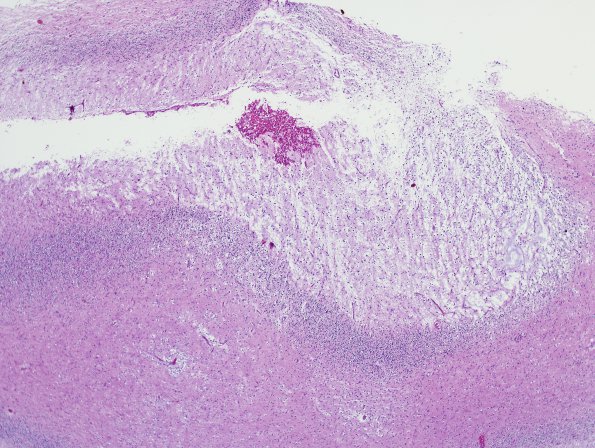

Washington University Experience | NEOPLASMS (NEURONAL) | DNET | 13A2 DNET, cerebellum (Case 13) H&E 1

13A2 DNET, cerebellum (Case 13) H&E 1